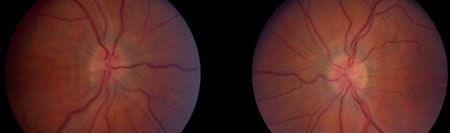

Signs that may be found on examination include optic disc swelling, sixth nerve paresis, and disturbances in sensory visual function. Visual field loss is ubiquitous, and the prototype pattern for early loss is enlargement of the blind spot and inferonasal loss.[35] The modified Dandy criteria can be used as diagnostic criteria.[36][37][Figure caption and citation for the preceding image starts]: Bilateral disc oedemaFrom the personal collection of Dr M. Wall; used with permission [Citation ends].

[Figure caption and citation for the preceding image starts]: Bilateral disc swelling settledFrom the personal collection of Dr M. Wall; used with permission [Citation ends].